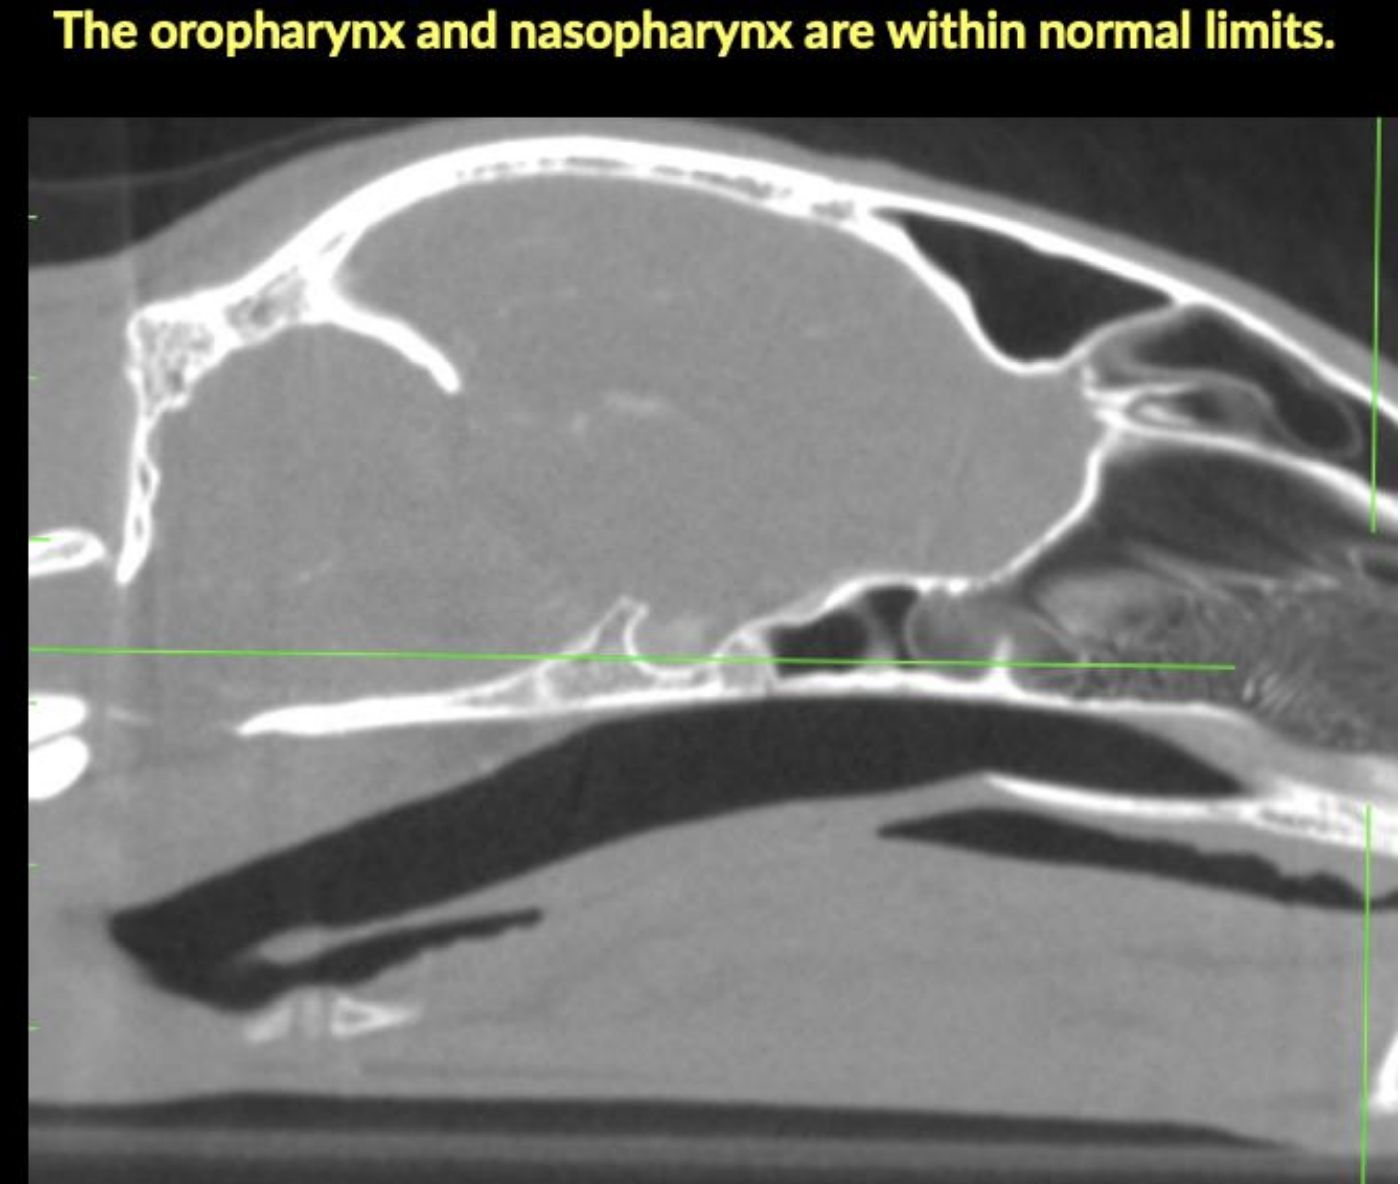

On the right, a sagittal CT image showing the normal oropharynx and nasopharynx.

The nasal cavities and frontal sinuses are within normal limits. The oropharynx and nasopharynx are within normal limits. The regional lymph nodes, medial and lateral retropharyngeal are moderately enlarged. The mandibular lymph nodes are within normal limits. The globes, retrobulbar spaces, and brain appear within normal limits.